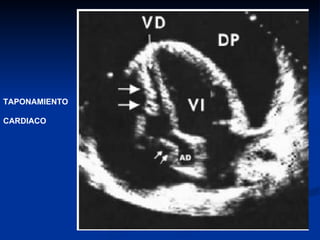

TAPONAMIENTO CARDIACO: SIGNOS ECOCARDIOGRAFICOS Cambios respiratorios anormales en las dimensiones  ventriculares  durante el ciclo respiratorio. Colapso de AD y VD. Colapso de cavidades izquierdas. Dilatación de VCI con ausencia de variaciones respiratorias. Variaciones respiratorias exageradas en los flujos mitral, aórtico y  tricuspídeo.

TAPONAMIENTO CARDIACO: SIGNOSECOCARDIOGRAFICOS Cambios respiratorios anormales en las dimensiones ventriculares durante el ciclo respiratorio. Colapso de AD y VD. Colapso de cavidades izquierdas. Dilatación de VCI con ausencia de variaciones respiratorias. Variaciones respiratorias exageradas en los flujos mitral, aórtico y tricuspídeo.